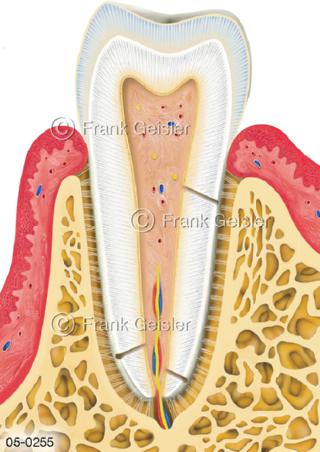

Bildergalerie Skelettsystem

Bilder zum Skelettsystem zeigen die Stützstruktur des menschlichen Körpers, die Knochen, eine besonders harte Form des Bindegewebes und Stützgewebes, welche das menschliche Skelett bildet, die Knochen des Stammes, der Extremitäten sowie der Gelenke